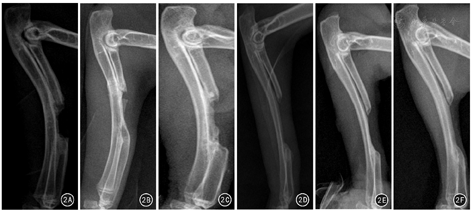

X线图像显示,术后第4周:A1组、A2组桡骨断端有大量不均匀低密度新生骨痂影,且A1组断端基本充满新生骨,A2组桡骨断端尚存在缺损空腔;B1、B2组桡骨断端仅有极少量新生骨生成。术后第8周:A1组桡骨断端有连续性骨痂通过,轮廓欠规则,密度低于正常骨皮质;A2组缺损面积较前稍减小,部分髓腔闭塞;B1、B2组桡骨断端低密度新生骨量增多,缺损空腔面积变化不明显。术后第12周:A1组标本均愈合,髓腔再通;A2、B1、B2组桡骨断端硬化,髓腔闭合,中央为软组织影。见图1、图2。

术后各时间点X线Lane-Sandhu评分显示:组内缺损面积不同的亚组间比较,A1组评分均高于A2组,差异均有统计学意义(P值均<0.05);B1组与B2组评分比较,差异均无统计学意义(P值均>0.05)。组间缺损面积相同的亚组间比较:A1组、A2组评分分别高于B1组、B2组,差异均有统计学意义(P值均<0.05)。见表1。